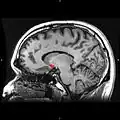

Approximate location of the nucleus accumbens in the brain